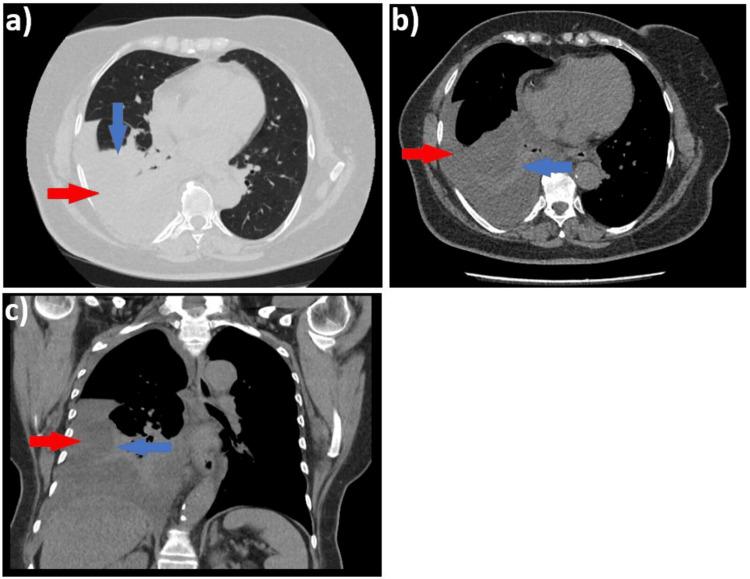

We present the clinical case of a 58-year-old female patient, a smoker with occupational exposure to respiratory toxins, who was admitted to our clinic following evaluation in an emergency department, where she was diagnosed with a moderate right pleural effusion. Upon admission, the patient exhibited respiratory symptoms, including progressive dyspnea with a moderate exertion threshold, right posterior pleuritic chest pain radiating anteriorly, occasional episodes of low-grade fever, and persistent febrile symptoms lasting approximately two weeks. In this clinical context, the diagnostic process was guided by the presence of right pleural effusion syndrome, which was refractory to conservative medical therapy. This necessitated a careful and stepwise expansion of investigations, ultimately leading to the diagnosis of malignant pleural mesothelioma. This case underscores the diagnostic challenges posed by pleural effusion, the necessity of adhering to the diagnostic algorithm, and the critical role of the multidisciplinary team. The diagnostic approach, often complex and challenging, necessitates a multidimensional strategy that integrates the correlation and synthesis of data obtained through anamnesis, alongside advanced diagnostic procedures such as pleural biopsy, which remains the gold standard. This comprehensive process is essential for formulating a diagnostic suspicion, with the final diagnosis intended to be one of exclusion.

摘要

我们介绍了一名58岁女性患者的临床病例,该患者有吸烟史且职业性接触呼吸道毒素,在急诊科评估后被收治入我院,在急诊科她被诊断为中度右侧胸腔积液。入院时,患者出现呼吸道症状,包括中度活动量时逐渐加重的呼吸困难、放射至前胸的右侧后胸膜炎性胸痛、偶尔的低热发作以及持续约两周的发热症状。在此临床背景下,诊断过程以右侧胸腔积液综合征的存在为指导,该综合征对保守药物治疗无效。这就需要谨慎且逐步地扩大检查范围,最终确诊为恶性胸膜间皮瘤。该病例强调了胸腔积液带来的诊断挑战、遵循诊断流程的必要性以及多学科团队的关键作用。诊断方法通常复杂且具有挑战性,需要一种多维策略,将通过问诊获得的数据的相关性和综合分析与先进的诊断程序(如胸膜活检,其仍是金标准)相结合。这一全面的过程对于形成诊断怀疑至关重要,最终诊断旨在排除其他可能。